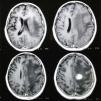

En julio de 2017, luego de 50días de tratamiento para toxoplasmosis del SNC, se realizó una nueva RM de cerebro con gadolinio que evidenció la aparición de una imagen nueva, de aspecto nodular, localizada en la convexidad frontal izquierda, isointensa en T1 y Flair, de señal heterogénea en T2, con realce en anillo tras la administración del contraste intravenoso y con presencia de edema vasogénico perilesional que provocaba efecto de masa y desplazamiento de las estructuras de la línea media (figs. 1 y 2). El foco motor progresó a hemiplejía braquiocrural derecha con empeoramiento del trastorno deglutorio y sensorio alternante. La TC de tórax no mostró lesiones. Se decidió realizar una biopsia cerebral estereotáxica (fig. 3), con obtención de material purulento, amarronado, del aspirado de la lesión (fig. 4). La tinción de Ziehl-Neelsen del material cerebral fue negativa, al igual que el examen de Gene Xpert® (MTB/RIF GeneXpert®) para detección de micobacterias. La tinción de Gram, la serología para Chagas y la parasitemia también resultaron negativas. En el examen micológico en fresco del material cerebral obtenido se observaron hifas hialinas tabicadas de un Eumicete (fig. 5), y con la tinción de Grocott, hifas ramificadas en ángulo agudo (fig. 6). En el cultivo en medio de Sabouraud-miel y agar infusión cerebro corazón a 28 y 37°C desarrolló Aspergillus sección fumigati.

El cuadro clínico de los aspergilomas cerebrales es inespecífico y no difiere de otros abscesos del SNC. Debe tenerse en cuenta que del 25 al 30% de los casos son asintomáticos y resultan hallazgos de las neuroimágenes, que siempre deben realizarse en pacientes con diagnóstico de aspergilosis invasora11. En los pacientes sintomáticos predominan la cefalea, los déficits neurológicos focales, los trastornos visuales, cambios en el estado de conciencia y convulsiones con rápida progresión de la sintomatología11. Los métodos de diagnóstico por imágenes (TC y RM) muestran lesiones focales, con refuerzo del contraste en anillo, edema perilesional y efecto de masa sobre las estructuras de la línea media, como se pudo observar en la paciente que se describe. El diagnóstico diferencial en pacientes con sida incluye la criptococosis (criptococomas), la tuberculosis (tuberculomas y abscesos), la toxoplasmosis, la nocardiosis y los chagomas10,12,13. Los criptococomas son más frecuentes en pacientes VIH negativos que en enfermos con sida. Estas lesiones focales o abscesos predominan a nivel de las regiones córtico-subcorticales de los lóbulos frontales y temporales14.